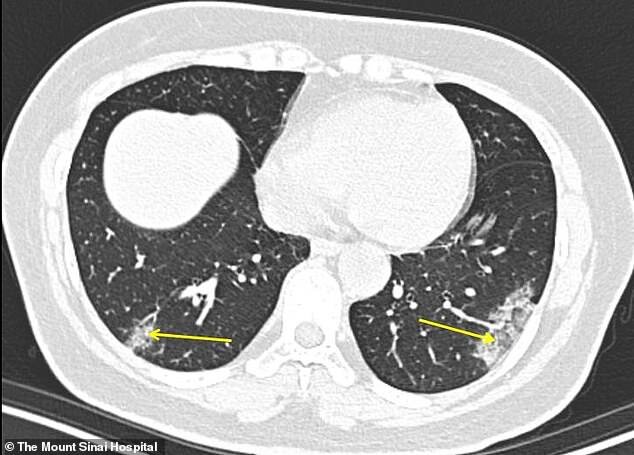

تبسم مهر - به گزارش ایسنا و به نقل از دیلی میل، بنابر گزارش‌ها سی تی اسکن 4 روز زودتر می‌تواند به پزشکان در شناسایی بیماران مبتلا به کرونا ویروس کمک کند چراکه پزشکان توسط آن می‌توانند میزان تخریب بافت ریه افراد مبتلا به این بیماری را به راحتی مشاهده کنند.

یک مطالعه جدید نشان می‌دهد که سی تی اسکن ممکن است در تشخیص سریعتر کروناویروس به کادر پزشکی کمک کند. پزشکان بیمارستان مونت سینای در نیویورک اولین کسانی بودند که در ایالات متحده اسکن ریه بیماران مبتلا به این بیماری بسیار مسری را تجزیه و تحلیل کردند. آنها گفتند که می‌توانند الگوهای خاصی در ریه‌ها را به عنوان نشانگر ویروس، که با نام COVID-19 نیز شناخته می‌شود، شناسایی کنند.

محققان می‌گویند که این تشخیص سریعتر می‌تواند به آنها کمک کند تا فرایند قرنطینه کردن بیماران را زودتر و پیش از ظهور دیگر علائم این بیماری آغاز کنند. آنها با سی تی اسکن می‌توانند میزان تخریب بافت ریه افراد را مشاهده کنند و این کاری است که توسط اسکن‌های دیگر مانند اسکن اشعه ایکس قفسه سینه امکان‌پذیر نیست. بنابر گفته پزشکان ظاهرا ریه بیماران مبتلا به کرونا الگو و نشانه خاصی دارد که با بررسی سی تی اسکن می‌توان این بیماری را چند روز زودتر تشخیص داد.

طی این مطالعه که در مجله Radiology منتشر شده است، پژوهشگران سی تی اسکن 94 بیمار را در چهار مرکز پزشکی در چهار استان چین مورد تجزیه و تحلیل قرار دادند. بیماران بین 18 ژانویه و 2 فوریه بستری شده بودند و همه یا اخیرا به ووهان - مرکز شیوع بیماری - سفر کرده بودند یا با یک فرد آلوده در تماس بودند. رادیولوژیست‌ها اسکن را بررسی کردند و بر اساس زمان بروز علائم و زمان انجام سی تی اسکن، یادداشت‌برداری کردند. آن‌ها دریافتند توسط سی تی اسکن می‌توانند چند روز زودتر وضعیت تخریب بافت ریه را مشاهده کنند. این کار می‌تواند به پزشکان در تشخیص زودتر بیماران کمک بسیار بزرگی کند؛ چراکه با تشخیص زودتر عملیات قرنطینه و درمان زودتر آغاز می‌شود. تاکنون بیش از 82 هزار نفر در سراسر جهان به این ویروس آلوده شده‌اند و بیش از 2 هزار و 800 نفر نیز جان باخته‌اند.